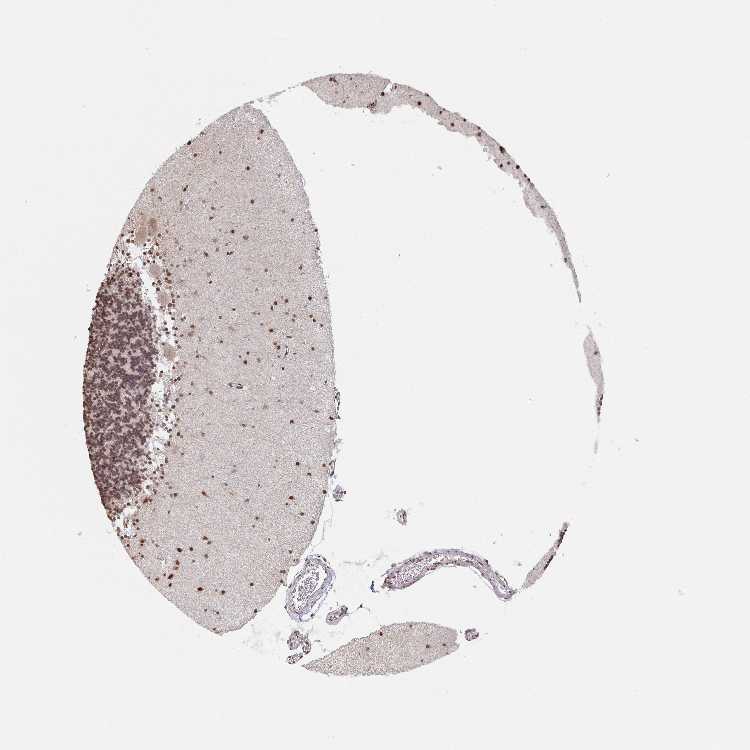

BRAIN CEREBELLUM Show tissue menu

CEREBELLUM - Expression summary

Protein expression

Cerebellumi

On the top, protein expression in current human tissue, based on all annotated cell types, is reported with the units not detected (n), low (l), medium (m) and high (h). Underneath, protein expression in each annotated cell type are reported using the same units.

Protein expression data is based on knowledge-based annotation. For genes where more than one antibody has been used, a collective score is set.

If knowledge-based annotation could not be performed for a gene, no data is displayed here. View antibody staining data further down this page.

Cells in granular layer: Medium

Cells in molecular layer: High

Purkinje cells: Medium

CEREBELLUM - Antibody stainingi

Antibody staining in the annotated cell types in the current human tissue is reported as not detected, low, medium, or high, based on conventional immunohistochemistry profiling in selected tissues. This score is based on the combination of the staining intensity and fraction of stained cells.

Each image is clickable and will lead to virtual microscopy that enables deeper exploration of all samples and also displays staining intensity scores, fraction scores and subcellular localization as well as patient and tissue information for each sample.

Antibody HPA035098Antibody CAB016398

Purkinje cells MediumHigh

Cells in granular layer MediumNot detected

Cells in molecular layer HighLow